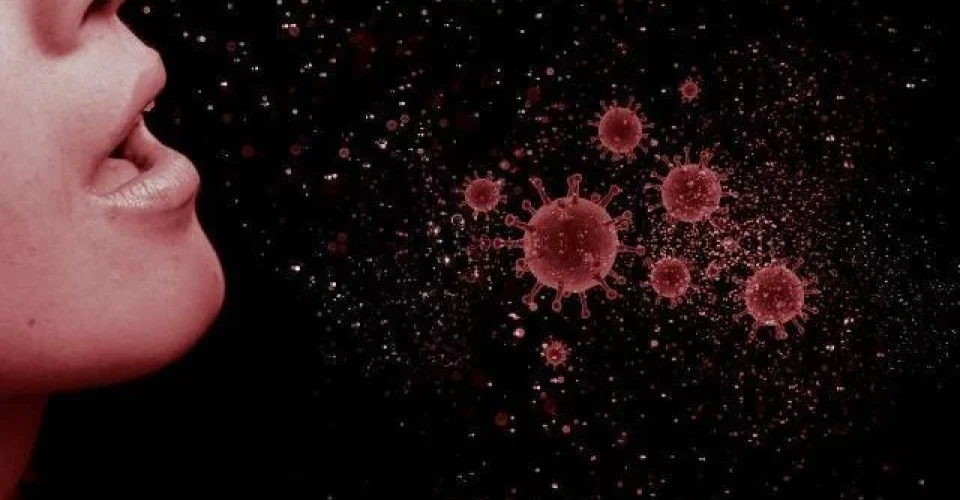

Cinco anos após o surgimento da covid-19, que desencadeou uma das maiores crises sanitárias da história e causou quase 7 milhões de mortes em todo o mundo, um novo surto viral na China está sobrecarregando o sistema de saúde local e chamando a atenção da Organização Mundial da Saúde (OMS). Desta vez, o problema é causado pelo metapneumovírus humano (HMPV), um patógeno pouco conhecido.

Os sintomas do HMPV são semelhantes aos das gripes comuns, incluindo febre, tosse e dificuldade para respirar. Alguns cientistas alertam que ele pode ser tão contagioso quanto o coronavírus. Redes sociais estão repletas de vídeos mostrando hospitais lotados, enquanto alguns internautas sugerem que a doença pode ser resultado de uma combinação de vários vírus.

A OMS monitora o avanço do HMPV e avalia os riscos potenciais de um surto global. Embora ainda não se tenha registrado disseminação significativa fora da China, a situação exige vigilância. O histórico recente da pandemia de covid-19 reforça a importância de uma resposta rápida e coordenada a novos patógenos.